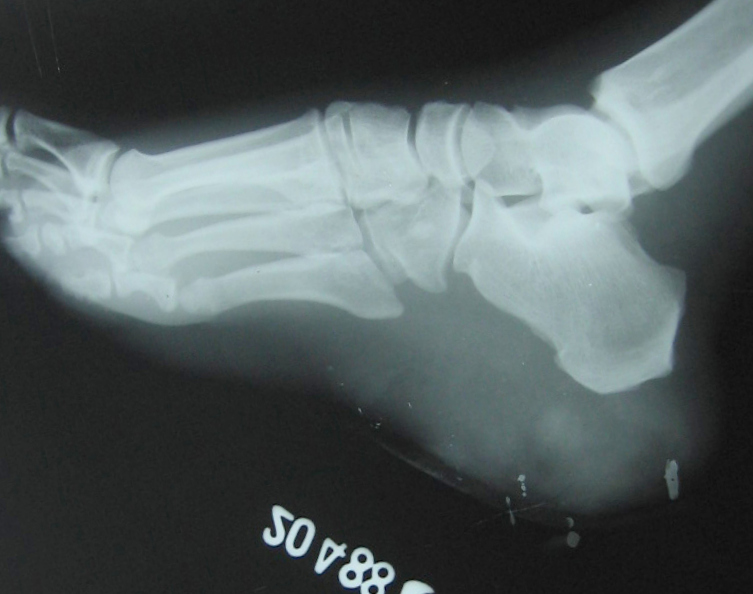

Fig.9 Rt foot lateral soft tissue radio graph -different patient